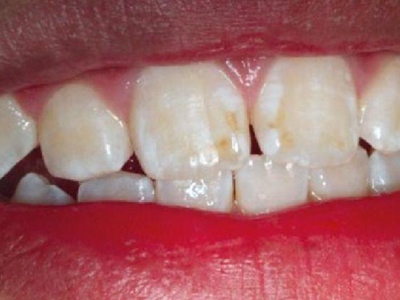

牙釉质发育不全牙齿白斑图

牙釉质发育不全患者可以仅仅出现牙齿色泽和透明度的改变,形成白垩色釉质,即类似于牙齿上有白斑,此时牙冠形态通常较完整。

牙釉质发育不全牙齿上出现白色的斑块图

牙釉质发育不全患者牙釉质表面出现白垩色釉质,表现为牙齿表面色泽不均匀,一般无自觉症状,并且此时牙冠形态较为完整,顶端出现小的缺损。